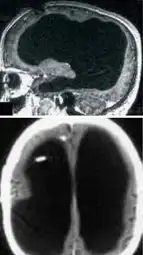

File: ClipboardImage.png 📥︎ (6.76 KB, 168x299) ImgOps

>>3005536

From what I remember reading people described him as generally normal, if a bit slow.

Considering his brain fucking looked like this, that's pretty damn impressive.